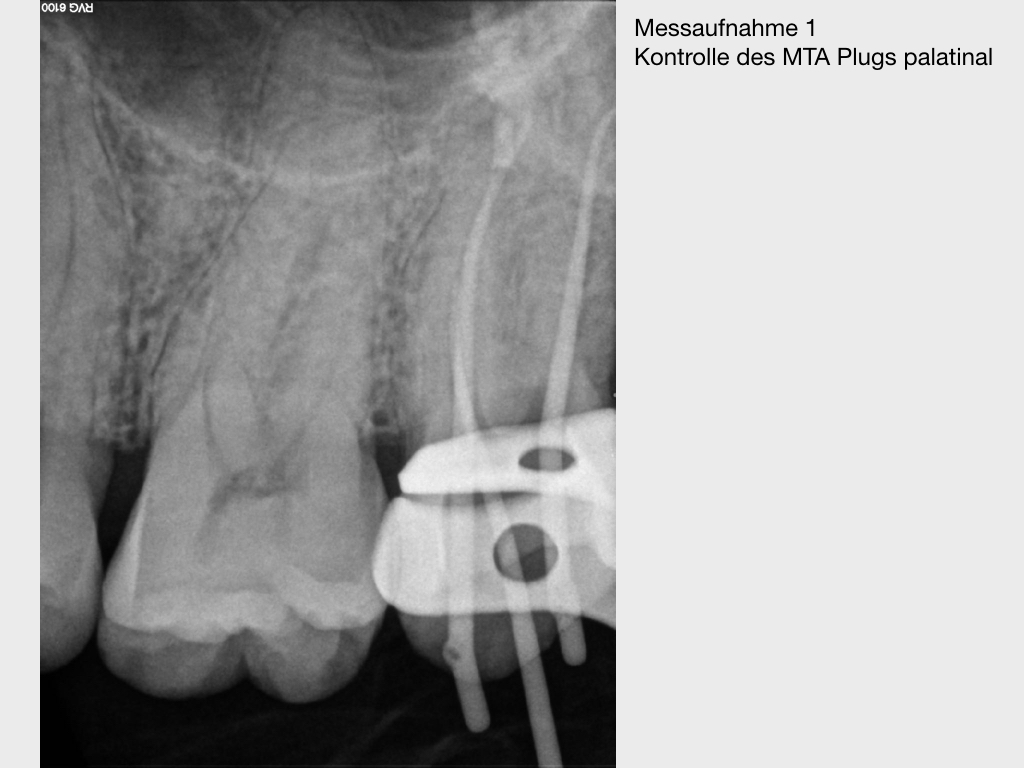

Pick1.012

Pick, Pick (2)